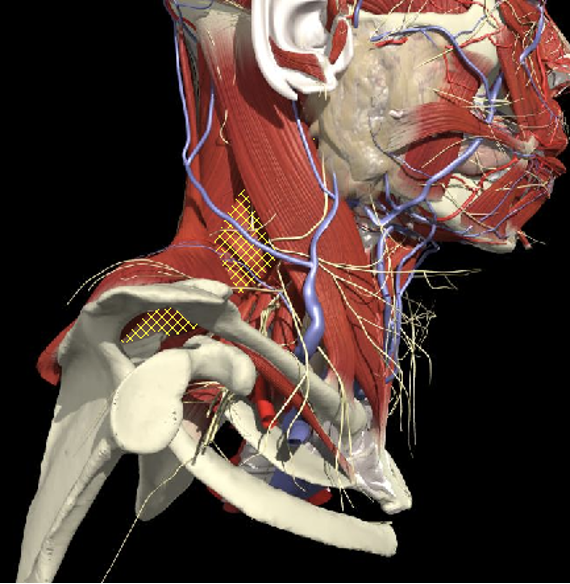

Structures to Avoid

Nerves in Posterior Triangle

Accessory nerve

Lies on LS, enters 1cm cranial to EP posterior border of SCM and runs on line to between middle and lower third of trapezius.

Should inject splenius and levator over 1cm above EP

Cervical plexus cutaneous branches

Mid point of posterior border

Inject levator above this point

Landmarks

Cervical plexus

Midpoint of SCM (EP)

Middle and lower third of Trapezius

Arteries

- Carotid artery

Midpoint anterior border of SCM

Vertebral artery

- Occipital bone or C2 towards midline is safe

Occipital artery

Avoid apex of posterior triangle